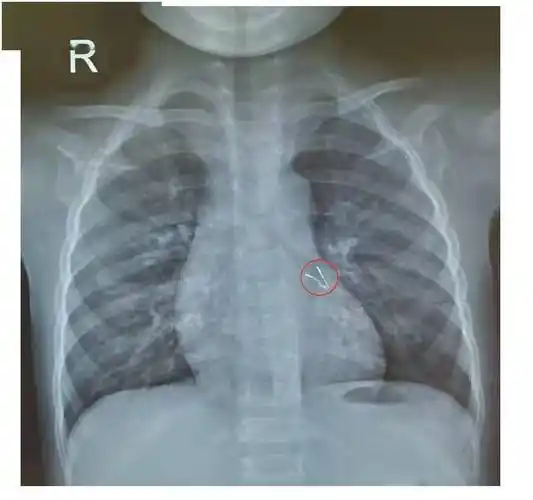

【x线讨论】支气管异物胸片病例讨论一例

图说:气道被异物占位 医院供图(下同)